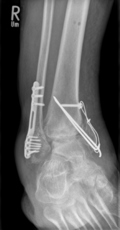

Oberschenkelamputation nach periprothetischer Tibiafraktur bei nicht sanierter periprothetischer Kniegelenksinfektion

Kurze Vorgeschichte: Herr S, ein 67-jähriger Patient, erhielt 2011 (Abbildung 1) bei ausgeprägter Gonarthrose eine primäre KTEP rechtsseitig. Im weiteren Verlauf zog er sich 2017 eine periprothetische Tibiafraktur zu, die mit einem Knieendoprothesenwechsel auf ein achsgeführtes Implantat (Abbildung 2) und Schaftverlängerung der Tibia im September 2017 ex domo therapiert wurde. Im Verlauf zeigten sich eine anhaltende Sekretion und eine partielle Nekrose am unteren Wundpol.

Eine Röntgendiagnostik des rechten Kniegelenkes in 2 Ebenen wurde eingeleitet. Hierbei zeigte sich eine stabil einsitzende Revisionsprothese ohne aktuelle Lockerungszeichen.

Procedere: Die stationäre Aufnahme erfolgte zunächst über die Kollegen der plastischen Chirurgie. Hier wurde im Dezember 2017 die Nekroseabtragung, ein Wunddebridement und eine Defektdeckung mittels M. Gatrocnemius-Lappenplastik und Spalthauttransplantation durchgeführt. Zudem erfolgte eine Neurolyse des N. peroneus. In den intraoperativ durchgeführten Abstrichen zeigte sich der Nachweis eines Candida parapsilosis, weshalb zunächst die antimykotische Therapie mit Fluconazol i.v. sowie anschließend oral erfolgte. Eine Peroneusfeder wurde rezeptiert.

Ende Novemeber 2018 erfolgte eine erneute Wiedervorstellung des Patienten in unserer Notaufnahme. Hierbei beklagte er rezidivierende lymphödematöse Schwellungszustände des Unterschenkels rechts, Knieschmerzen und radiologisch nachgewiesene Flüssigkeitsansammlung im Kniegelenk rechts. Eine Punktion des Kniegelenkes erfolgte im Dezember 2018, wobei sich eine chronische Infektion mittels Candida parapsilosis des rechten Kniegelenkes bestätigte.

Wir haben anschließend im März 2018 den Ausbau der einliegenden Kniegelenksprothese empfohlen, um den Infekt zu sanieren. Dies wurde jedoch seitens des Patienten abgelehnt.

Im weiteren Verlauf zeigten sich die Weichteile des rechten Unterschenkels zunehmend mazeriert und belegt. Zudem sei der Patient erneut gestürzt. Eine erneut durchgeführte Röntgendiagnostik zeigte erneut eine periprothetische Tibiafraktur (Abbildung 3) bei einliegender achsgeführter KTP mit langem tibialem Stem und bekanntem periprothetischem Infekt mit Candida parapsilosis. Wir haben die Befunde ausführlich mit dem Patienten besprochen und in Zusammenschau der Befunde schließlich die Indikation zur Oberschenkelamputation gestellt.

Diese konnte komplikationslos im Mai 2018 durchgeführt werden (Abbildung 4 und 5).

Womöglich hätte der drastische Schritt einer Amputation durch eine frühzeitige Prothesensanierung, welche jedoch durch den Patienten abgelehnt wurde, verhindert werden können.